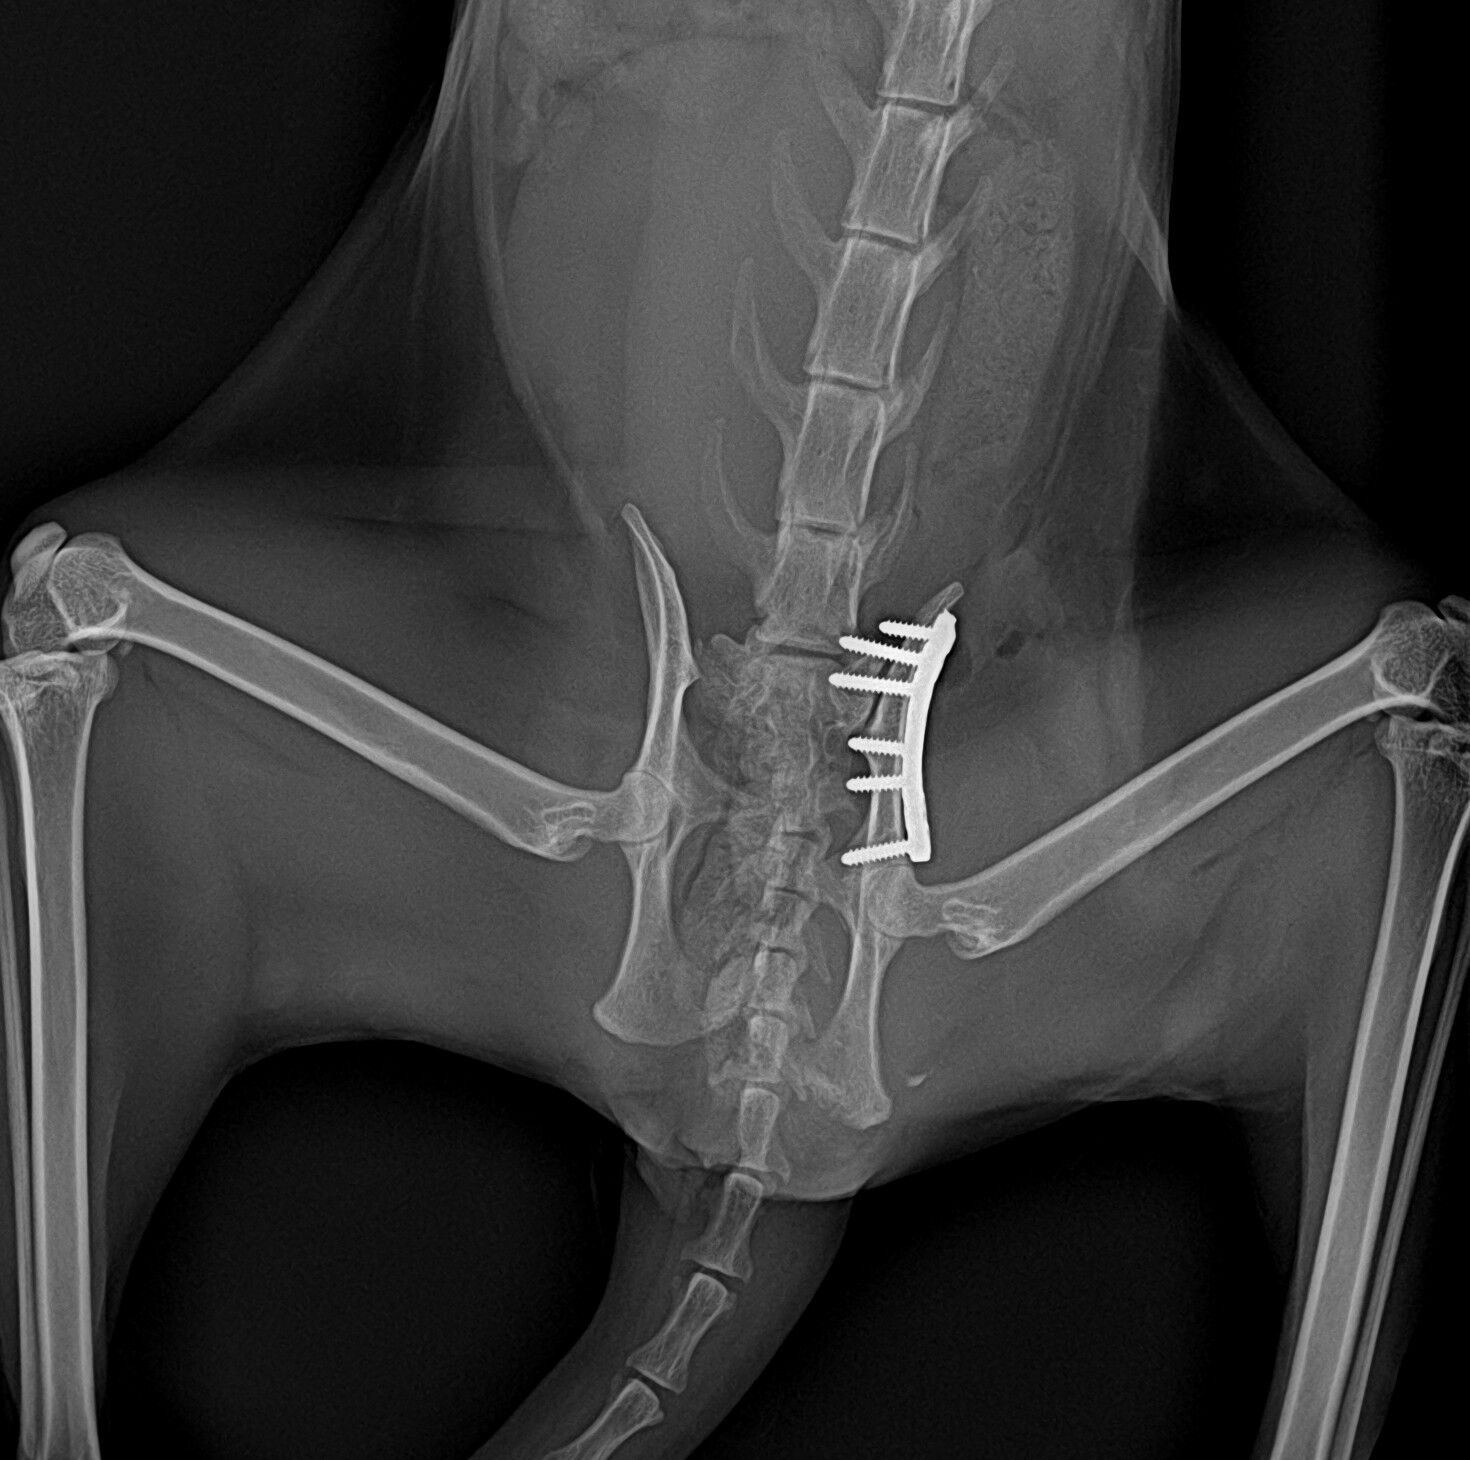

以下が仙腸関節の整復後の写真です。

骨盤骨折整復後ももう一つ食欲がなく強制給餌をしていましたが、仙腸関節脱臼整復後は食欲が出てきました。痛みがあって食欲がでなかったのしょう。脱臼整復後は順調に回復し退院していきましたが、まだまだ外に出すことはできません。1か月はケージレストで過ごさないとなりません。ネコちゃんは外で生活していると危険な目に遭うことが多いです。できればおうちの中で飼っていただきたいところですが、色々な事情があるとしょうがないですね。